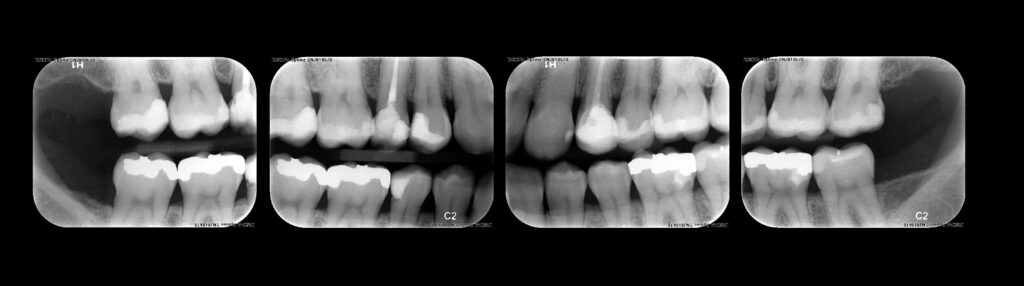

Radiografias Digitais

Interproximais